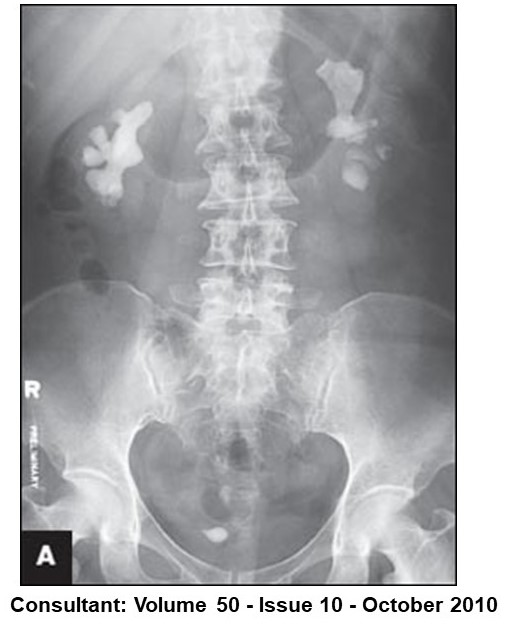

Struvite stones can enlarge & fill the renal calyces, producing a "staghorn" appearance

🔸Abdominal X ray (***Purine stones can be radiolucent)